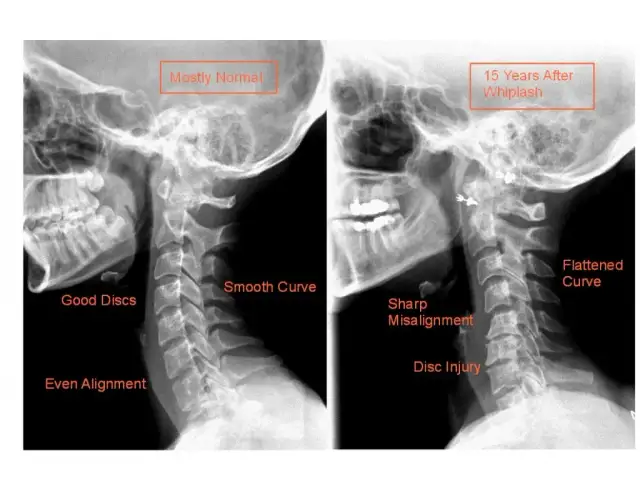

Poznaj objawy bólu kręgosłupa piersiowego i dowiedz się, co mogą oznaczać. Zrozum swoje dolegliwości i podejmij odpowiednie kroki w kierunku zdrowia.